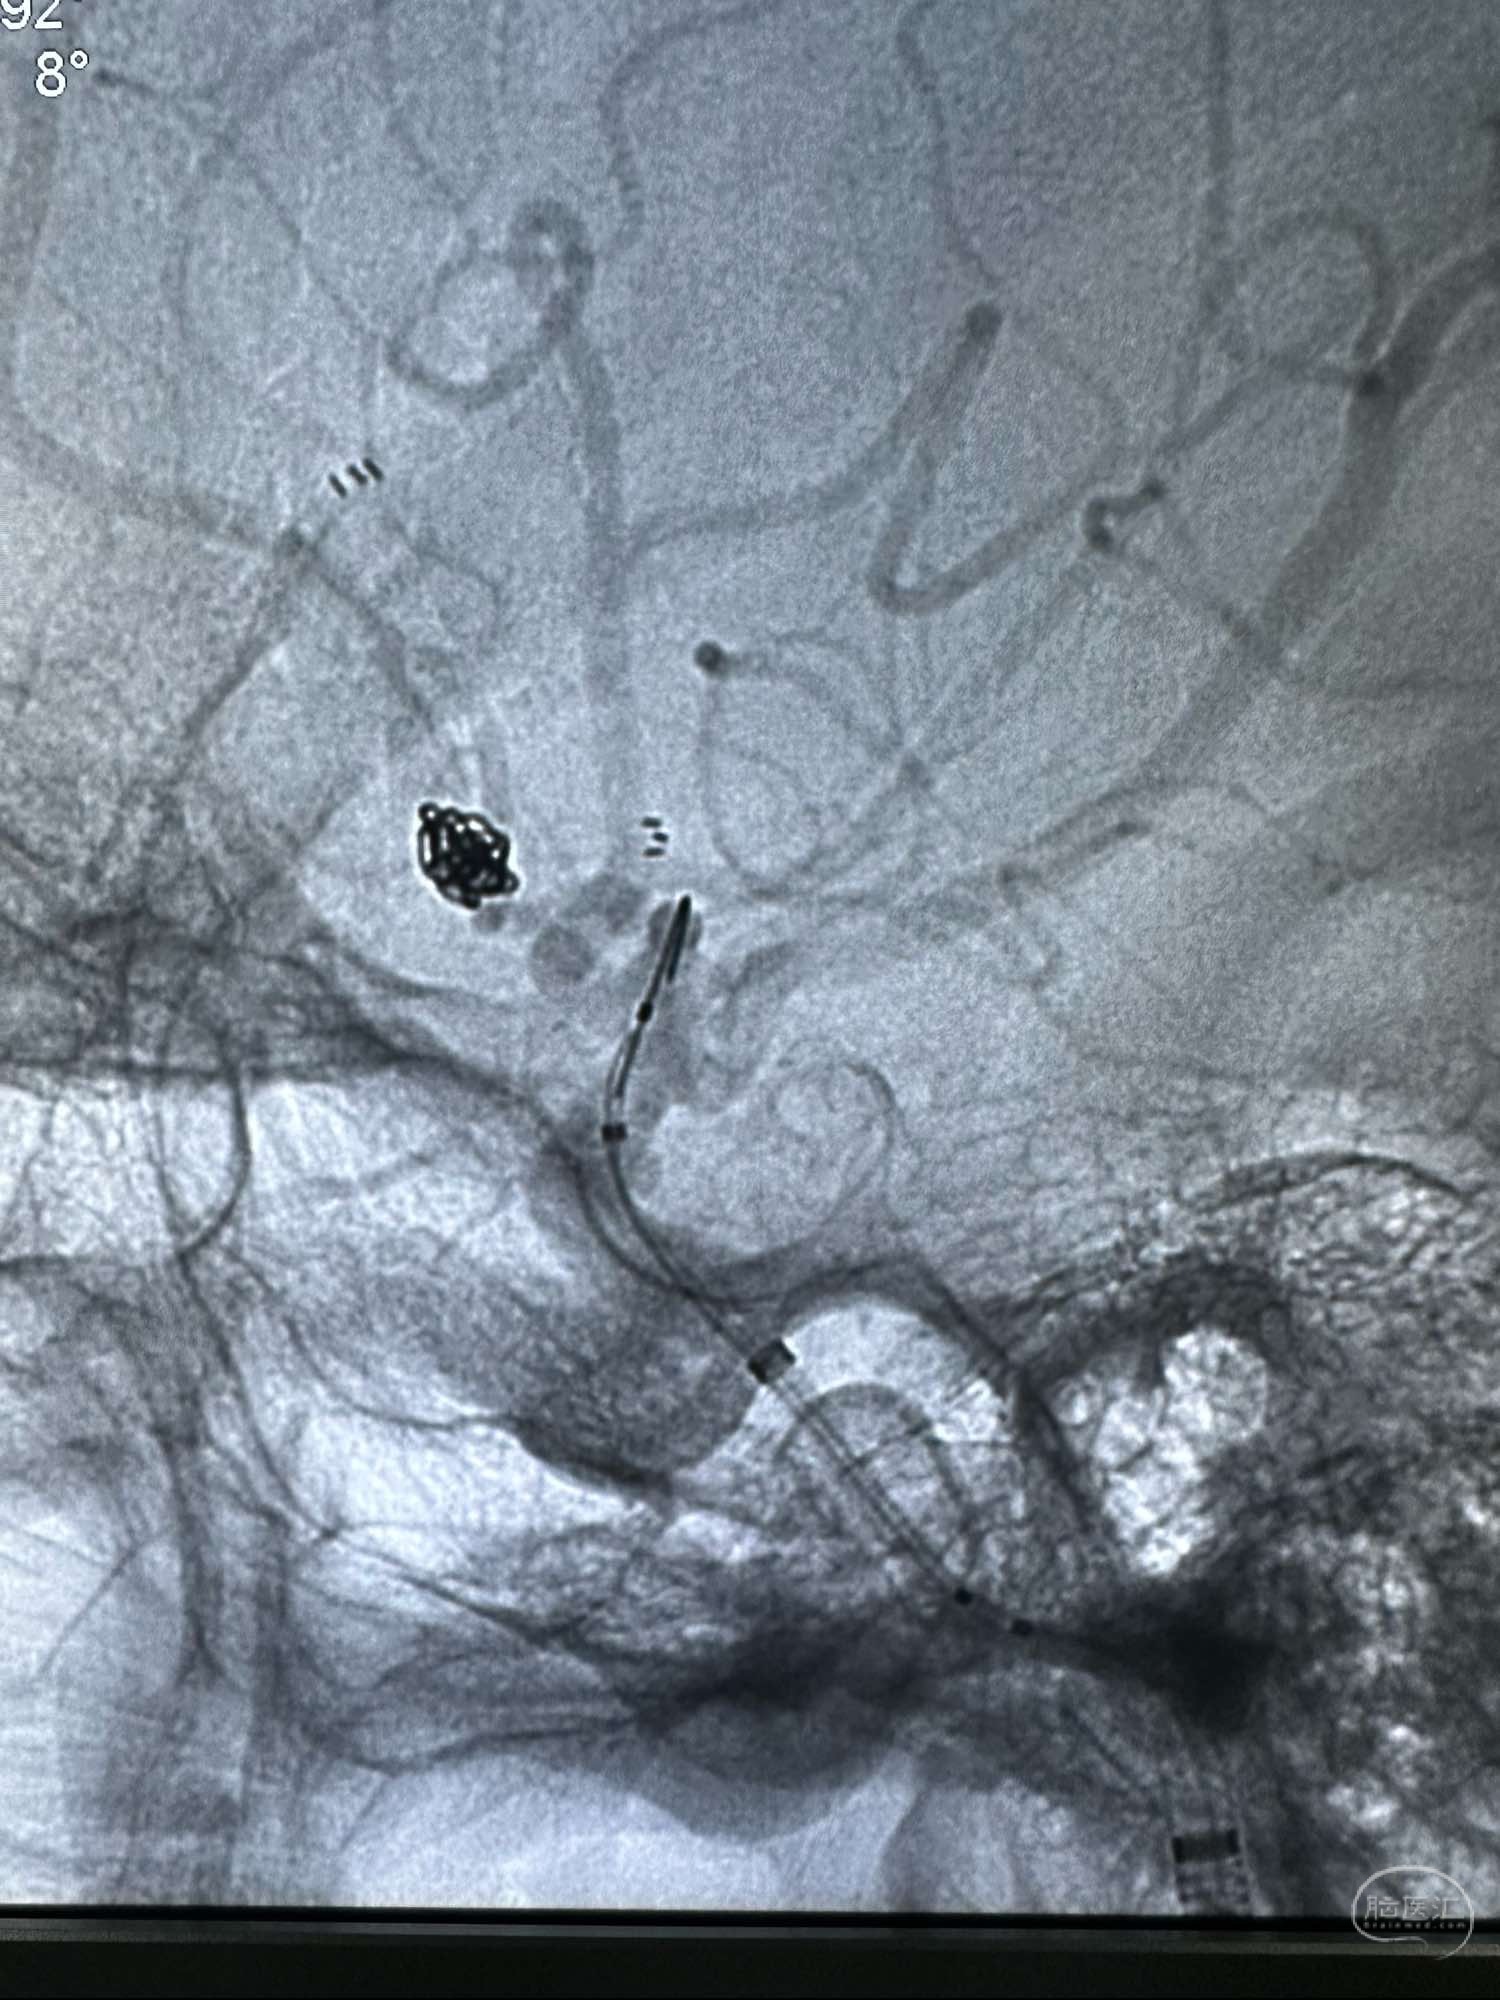

术前的右侧颈内动脉正位造影

工作角度,路径不好

术前的右侧颈内动脉正位造影

工作角度,路径不好